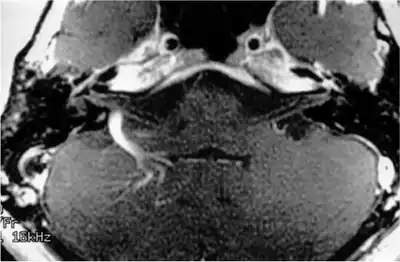

Magnetic resonance imaging

Individual with venous angioma of right cerebellum who presented with sensorineural hearing loss, image shows a prominent draining vein caused by venous angioma of right cerebellar hemisphere, which impinges on the vestibulocochlear nerve.

MRI scans can be used to identify gross structural causes of hearing loss. They are used for congenital hearing loss when changes to the shape of the inner ear or nerve of hearing may help diagnosis of the cause of the hearing loss. They are also useful in cases where a tumour is suspected or to determine the degree of damage in a hearing loss caused by bacterial infection or auto-immune disease. Scanning is of no value in age-related deafness.